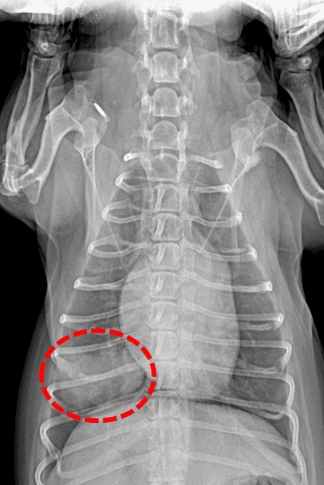

診斷過程通常需要多管齊下。獸醫可能會先聽診,然後建議做X光或超音波。X光是最基本的工具,可以看肺部的陰影變化。但如果腫瘤很小,X光可能看不出來,這時就需要進階檢查如CT掃描。

| 影像學檢查 | X光、超音波 | 查看肺部有無異常陰影 |

| 進階診斷 | CT掃描、活檢 | 確認腫瘤位置和類型 |